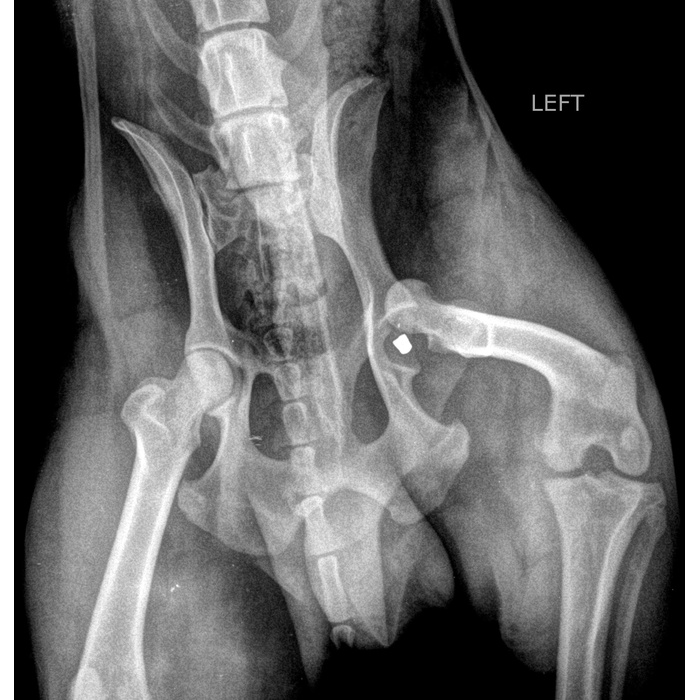

Паностеит у собак

Паностеит у собак 118 фотографий